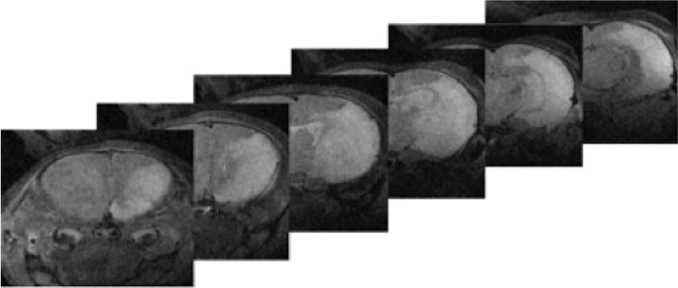

To assess in vivo the degree of HI injury, six high-field magnetic resonance (MR) images obtained from a single rat pup (P15) under anesthesia eight days after HI injury were obtained (Figure 1) (Agilent Magnex Scientific 11.1T 40 cm horizontal magnet at the University of Florida’s McKnight Brain Institute). The cortical damage including necrosis and white matter injury in the right hemisphere is clearly visible in this animal.

Figure 1. 11T T2 In vivo Magnetic Resonance Imaging of a P15 rat 8 days after Hypoxic-Ischemic injury. Cortical damage can be seen in the cortex, subcortical white matters, and hippocampus, represented by the white regions. This corresponds to the HI injury.

At P15 (8 days after HI injury), animals where anesthetized with isoflurane (2%) and scanned with an 11T MRI system (Agilent Magnex Scientific 11.1T 40 cm horizontal magnet at the University of Florida’s McKnight Brain Institute). The head of the rat pup was positioned in a custom-made cradle with an adjusted bite-bar to maintain head position. Anesthesia, respiration, and body temperature were monitored throughout the scanning process. T2-weighted 11 Tesla scans were acquired with 0.5-mm slices to assess the cortical damage throughout the brain because of the HI injury.